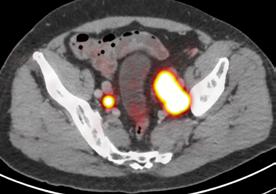

In the 2020-21 issue of Images, we shared the story of the U.S. Food and Drug Administration’s approval of Prostate-Specific Membrane Antigen (PSMA) PET imaging, based on research conducted at UC San Francisco and UCLA. The technique uses positron emission tomography in conjunction with a PET-sensitive drug that is highly effective in detecting prostate cancer throughout the body so that it can be better and more selectively treated. The PSMA PET scan also identifies cancer that is often missed by current standard-of-care imaging techniques.

In September 2021, a team led by Thomas Hope, MD, at UCSF and Jeremie Calais, MD, at UCLA, published a paper in JAMA Oncology (doi:10.1001/ jamaoncol.2021.3771) detailing the phase 3 diagnostic efficacy trial that led to FDA approval of PSMA PET.

What is the main focus of the JAMA Oncology paper?

The paper focuses on the role of 68Ga-PSMA-11 PET at time of initial staging. The goal was to compare the imaging results to nodes found at time of surgery in order to determine the sensitivity and specificity of PSMA PET. This study showed that PSMA PET has a high specificity for the detection of nodal metastases, although the sensitivity for small pelvic nodes was lower than expected.

Next up is to grow the use of PSMA PET for patient selection in PSMA radioligand therapy.

Currently there are no FDA approved agents for PSMA radioligand therapy, but we expect approval of 177Lu-PSMA-617 in the coming months, and so we will start using PSMA PET in this patient population.  Additionally, now that PSMA PET will be widely available, we will need to complete clinical trials in order to understand how to manage patients better based on the results of PSMA PET imaging studies. 

PSMA PET scan identifies cancer that is often missed by current standardof-care imaging techniques.